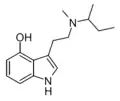

| MiPT | artificial | H | CH3 | CH(CH3)2 | N-Methyl-N-isopropyltryptamine | 96096-52-5 |